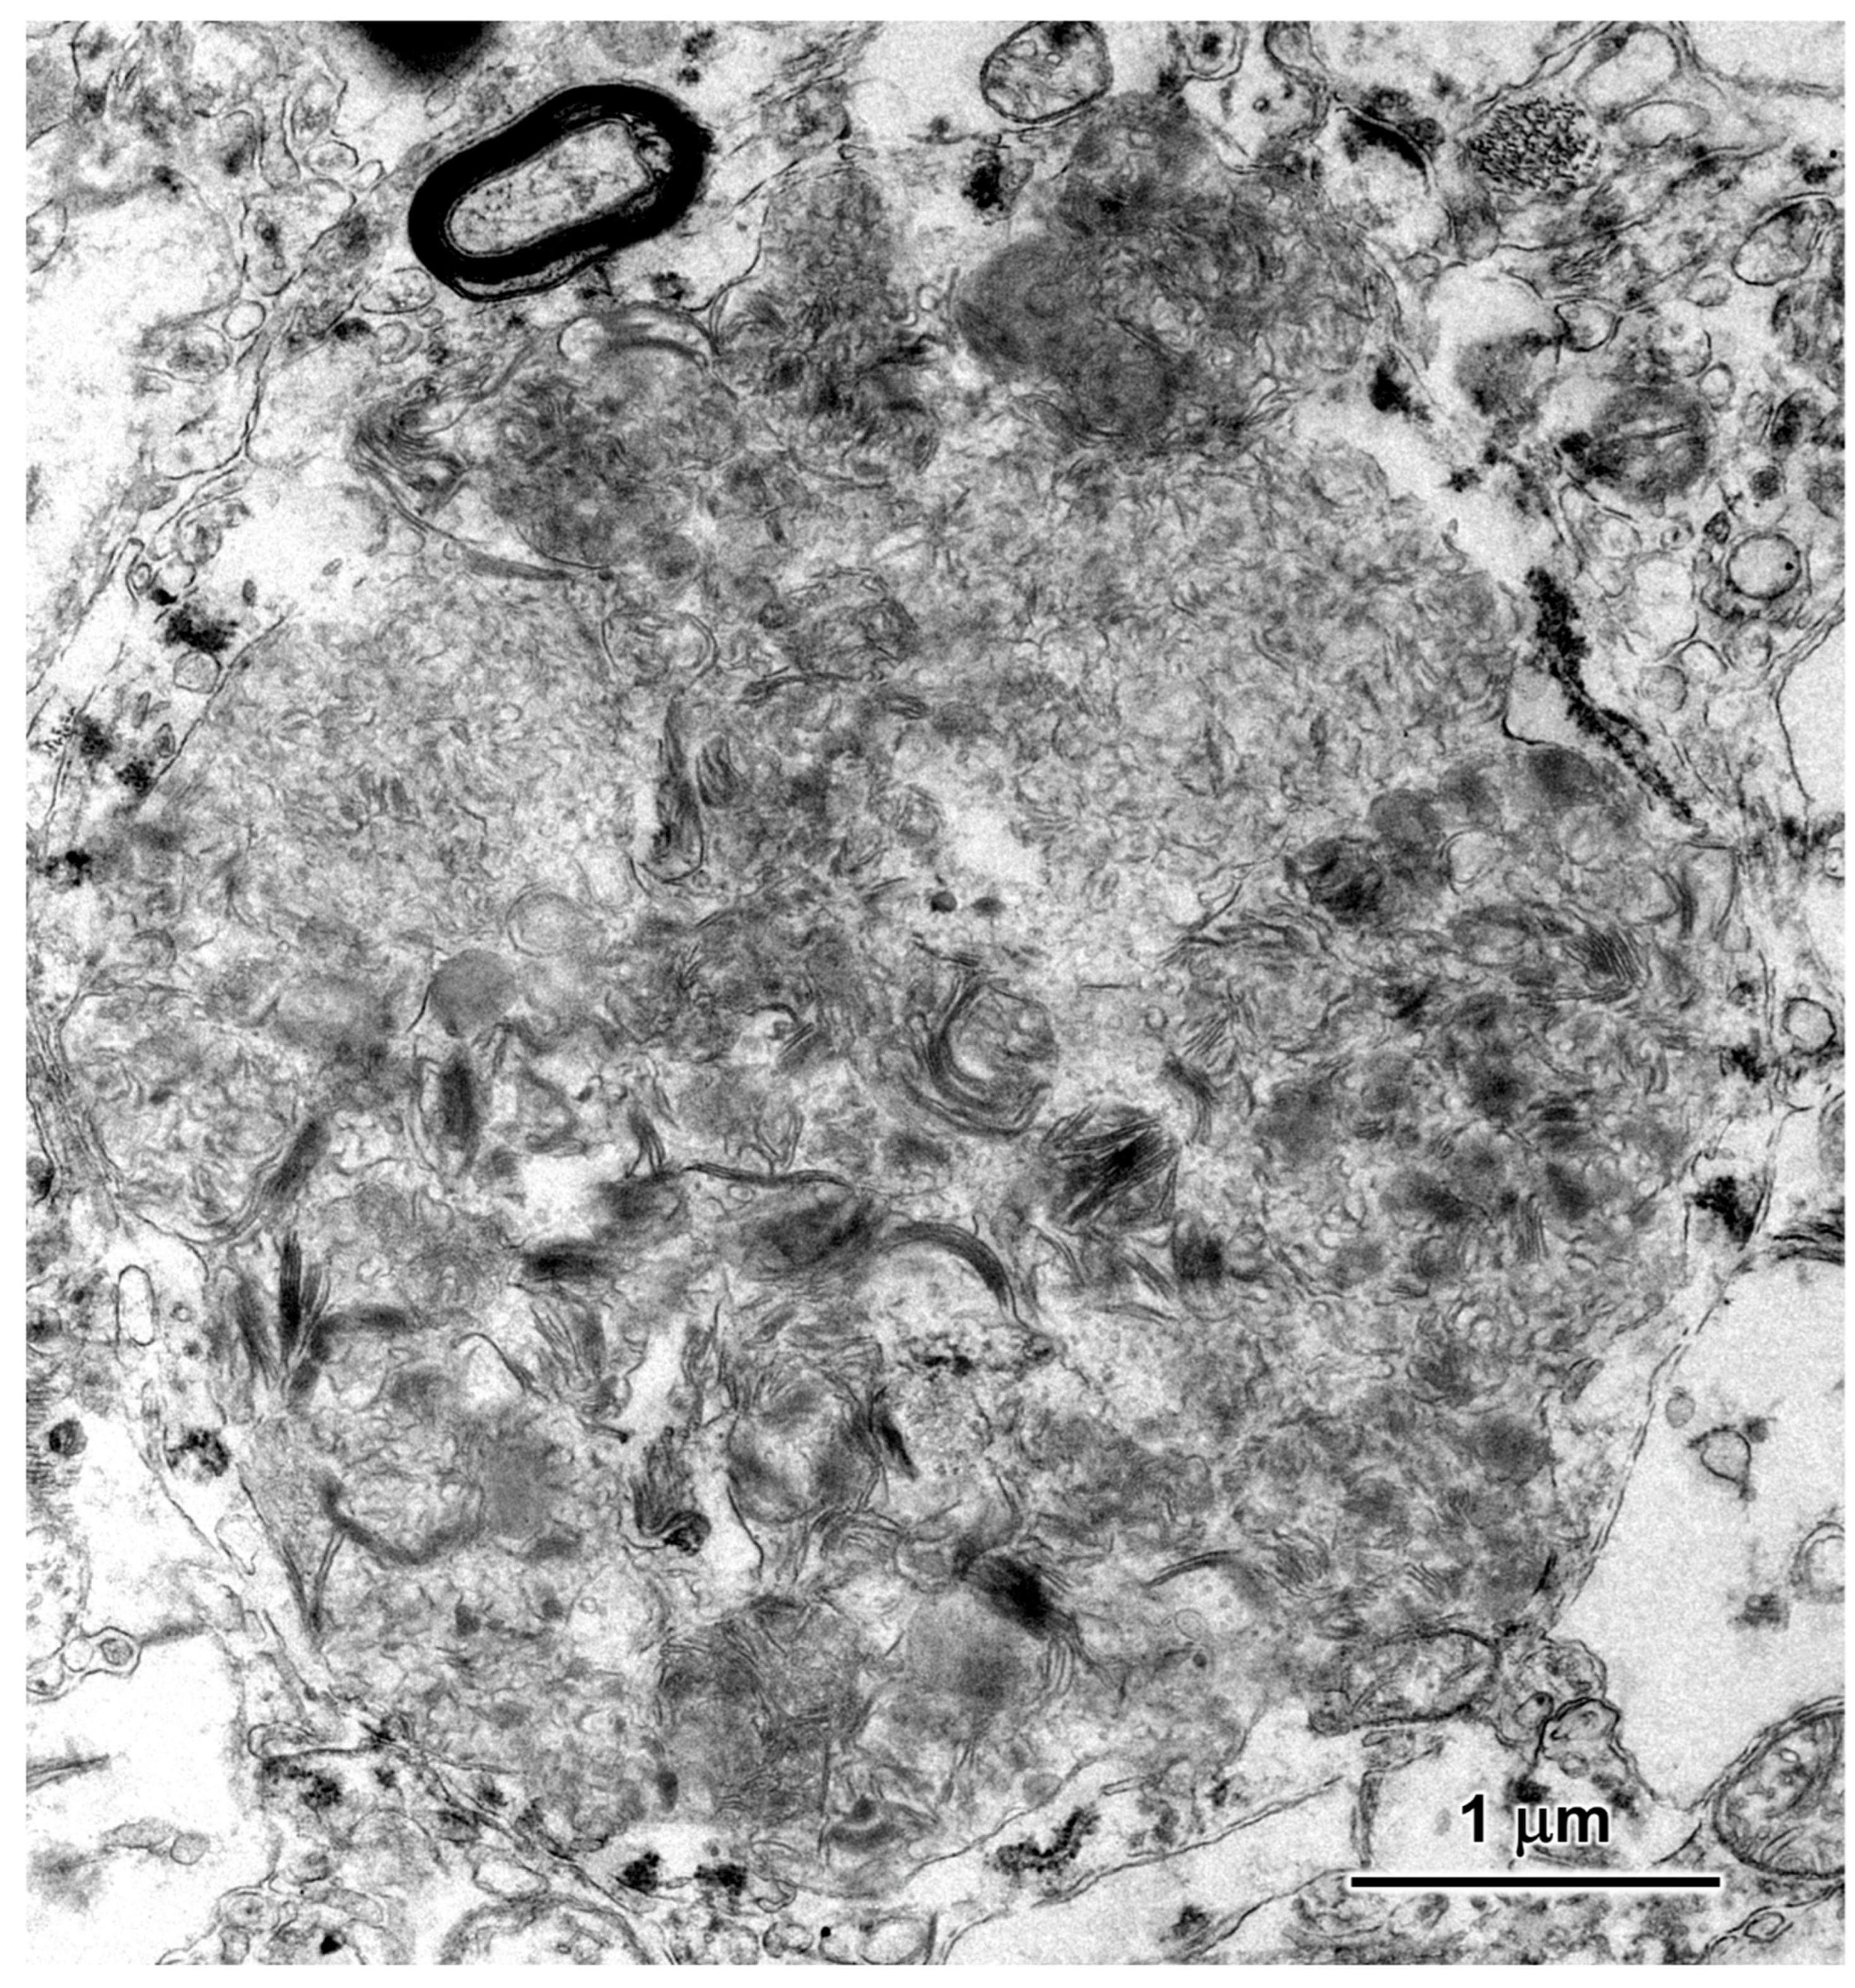

3.2. Microscopic Findings